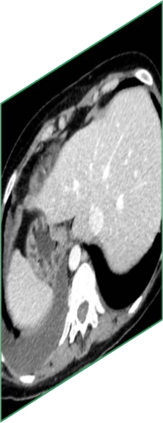

Due to the constraints of the imaging device and high cost in operation time, computer tomography (CT) scans are usually acquired with low intra-slice resolution. Improving the intra-slice resolution is beneficial to the disease diagnosis for both human experts and computer-aided systems. To this end, this paper builds a novel medical slice synthesis to increase the between-slice resolution. Considering that the ground-truth intermediate medical slices are always absent in clinical practice, we introduce the incremental cross-view mutual distillation strategy to accomplish this task in the self-supervised learning manner. Specifically, we model this problem from three different views: slice-wise interpolation from axial view and pixel-wise interpolation from coronal and sagittal views. Under this circumstance, the models learned from different views can distill valuable knowledge to guide the learning processes of each other. We can repeat this process to make the models synthesize intermediate slice data with increasing inter-slice resolution. To demonstrate the effectiveness of the proposed approach, we conduct comprehensive experiments on a large-scale CT dataset. Quantitative and qualitative comparison results show that our method outperforms state-of-the-art algorithms by clear margins.